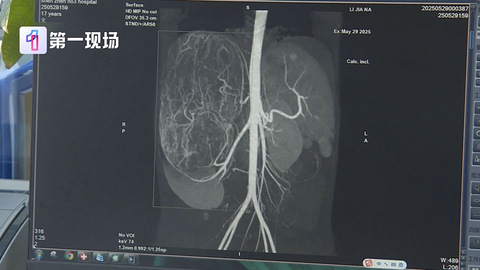

按摩致“脂肪瘤”破裂進ICU!醫(yī)生:這4種建議切除

很多人會在不經(jīng)意間,發(fā)現(xiàn)身上的某個部位長出來一個或者多個小疙瘩,摸起來軟軟的,還會活動,不痛不癢,沒有任何不適。 這個小疙瘩可能是脂肪瘤。 近日,浙江一位女士按摩時,感覺肚子不舒服,回家后感覺腹部變大且腹痛難耐,出現(xiàn)嘔吐腹瀉癥狀。就醫(yī)后經(jīng)全腹CT平掃顯示,其左腎占位,血管平滑肌脂肪瘤破裂大出血,術后送入ICU繼續(xù)觀察。 據(jù)悉,其左腎有個錯構瘤,但很小不影響生活,此次按摩將瘤子按破導致大出血。 脂肪